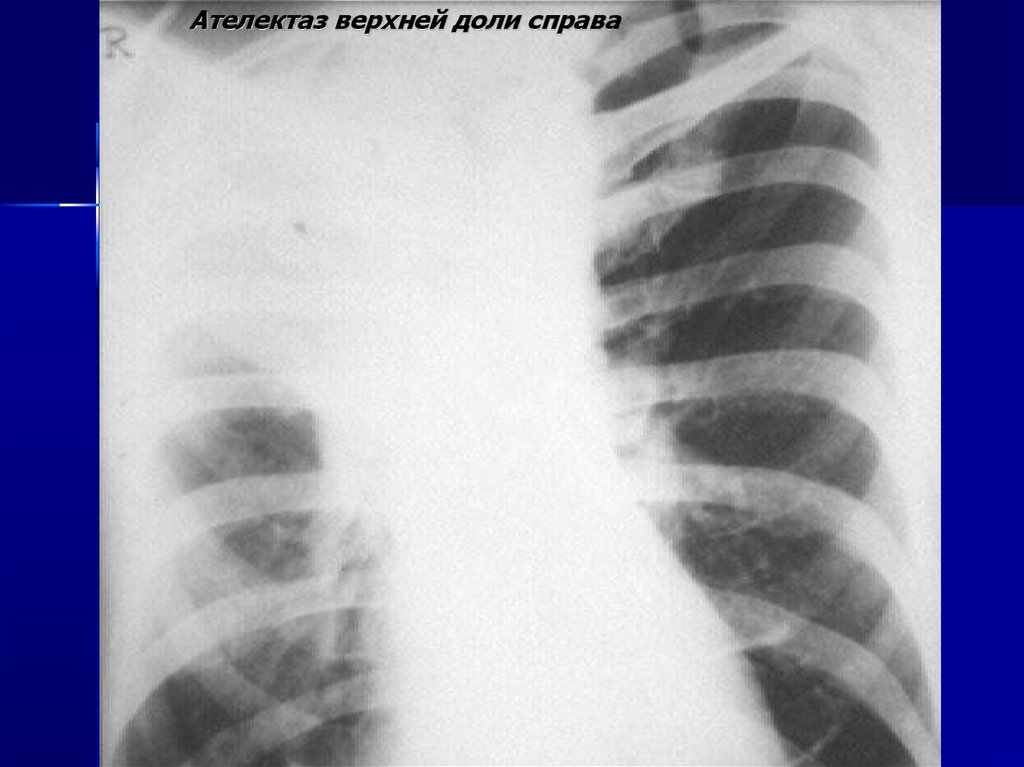

Ателектаз верхней доли справа